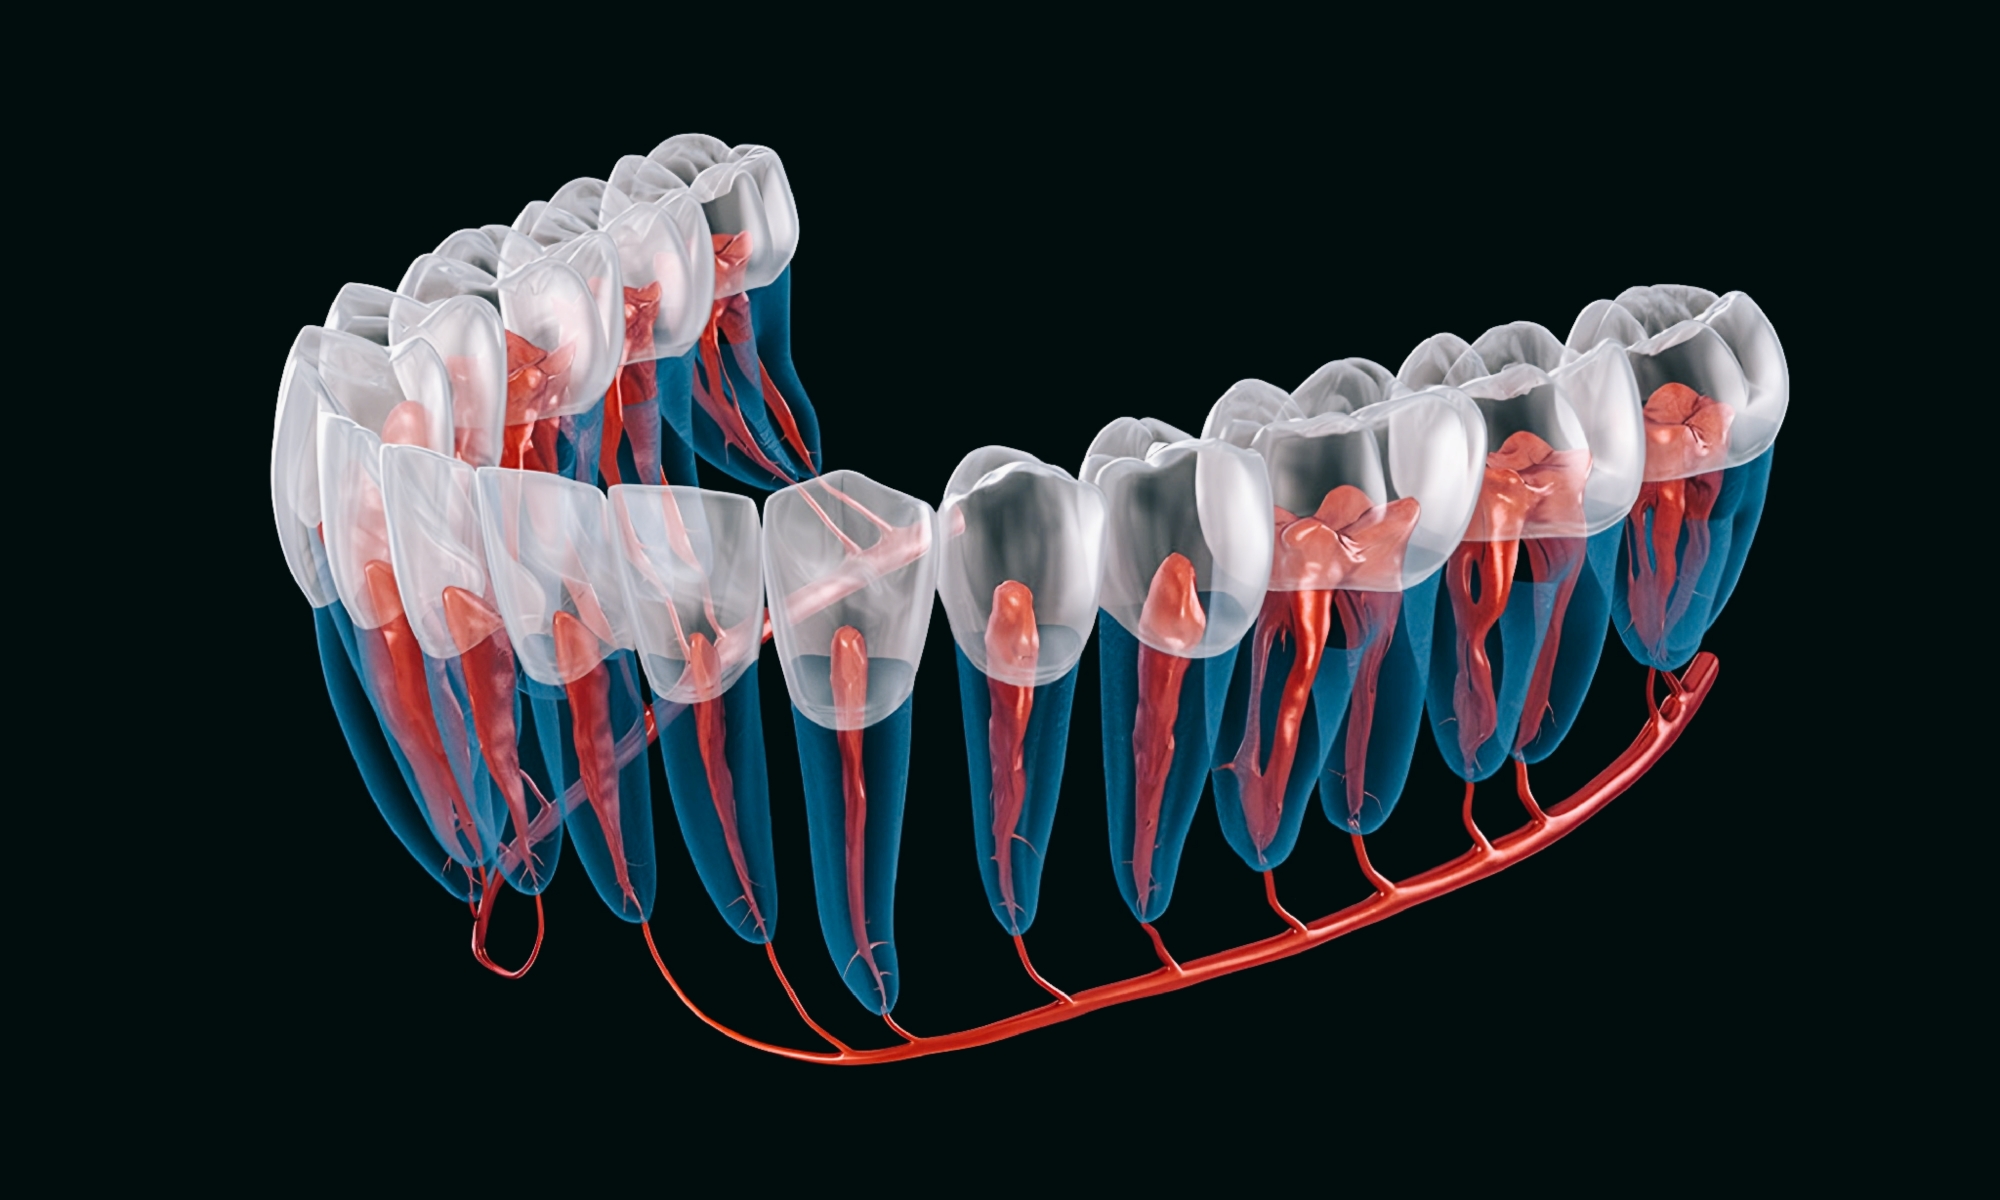

مغز دندان یا پالپ دندان (به زبان انگلیسی: Pulp) به رگها و اعصاب دندان می گویند. حفره مرکزی در تاج دندان، اتاق پالپ نامیده می شود. مجرای ریشه دندان را نیز کانال دندان نامیده می شود. در حالت عادی مغز دندان زنده و فعال است ولی پوسیدگیها و آزردگیهای رگها و عصبها باعث درد و سرانجام مرگ مغز دندان، و از بین رفتن مغز دندان می شود.